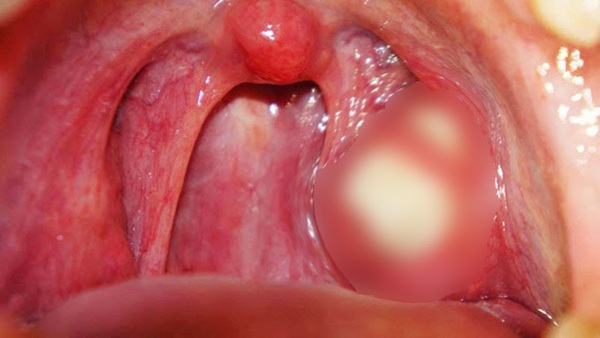

Sỏi Amidan (tonsil stone) - còn gọi là bã đậu amidan - là những khối nhỏ màu trắng vàng xuất hiện xung quanh 2 túi amidan trong vòm họng. Và nếu như bạn đang cảm thấy "kinh dị" lắm rồi thì tin xấu hơn đây: trong họng của bạn có thể đang có mấy cục này.

Bạn thậm chí sẽ chẳng biết chúng có tồn tại, vì nhiều lúc sỏi amidan "mọc" và ẩn nấp ngay đằng sau túi amidan của chúng ta.

Dành cho những người chưa biết, Amidan là hàng rào các tế bào lympho dùng để bảo vệ cơ thể chống lại sự xâm nhập của vi khuẩn. Và cũng chính vì phải "phơi mặt" ra hứng vi khuẩn nên nếu phải đối mặt với một đội quân vi sinh vật vượt quá khả năng xử lý, amidan sẽ bị viêm và sưng đỏ. Vậy thì sao chứ? Vấn đề ở đây là những viên sỏi amidan là loại thức ăn quá xuất sắc dành cho vi khuẩn.

Chúng sẽ sinh sôi tại đây, và đến khi đạt đủ số lượng, amidan của bạn sẽ bị sưng tấy nghiêm trọng, gây nên các triệu chứng khó chịu như ốm, sốt cao, buồn nôn, đau họng, ù tai...